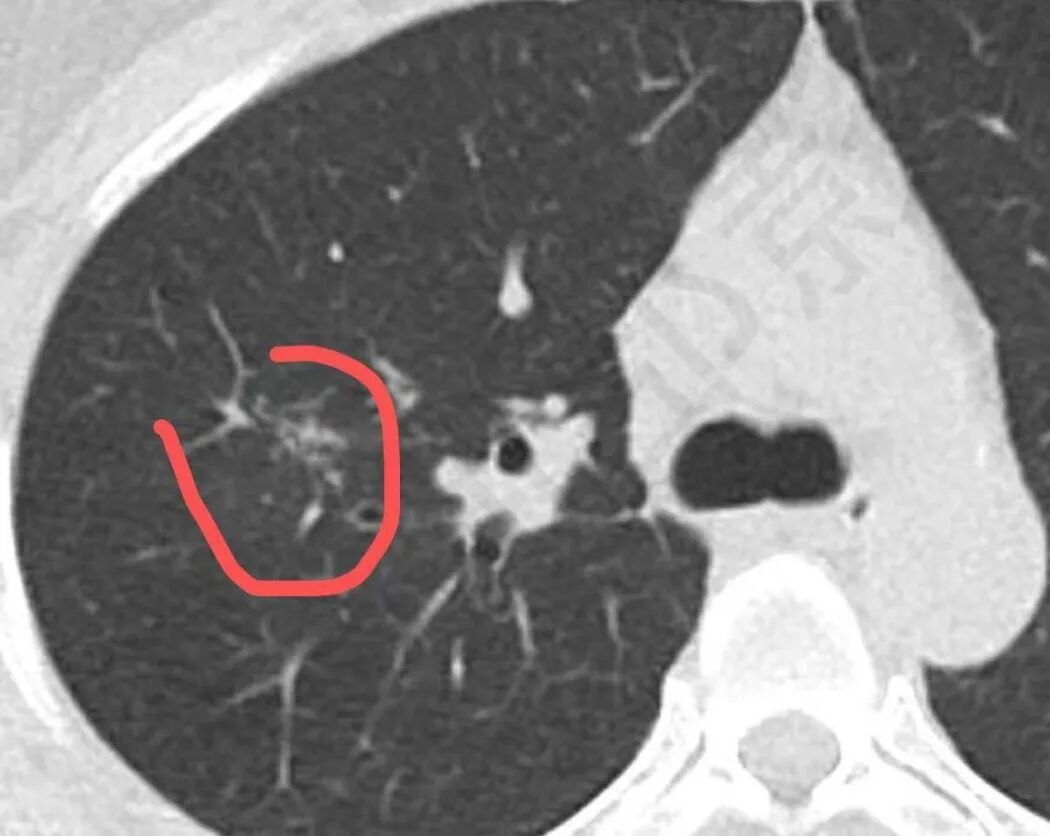

影像特点:右肺上叶混合磨玻璃影,边界清晰,结构松散,内有多结节堆积及支气管扩张影,可见小叶间隔增厚,并局部增厚的小叶间隔上亦存在微结节,胸膜侧可见纤细索条,病灶周围可见多发微结节影。

总体分析:从病灶分布来看符合结核的好发位置,影像表现也符合结核的多态性,且出现卫星灶。由于有边界清晰的GGO,需要鉴别腺癌,虽然此病例有边界清晰的GGO,但是它的GGO的边缘有结节感,呈多结节堆积,而腺癌的GGO缺乏这种“多结节堆积感”,另外,此病例也没有发现腺癌的胸膜凹陷征、毛刺征及月牙铲等。

一般来说,间质性结核主要是实性来源的;开始是气道播散为主,主要表现最多的是树芽征,然后是腺泡结节,相互之间可融合形成片状,往往这些病人有个前提,免疫力相对低下,然后侵袭到附近的间质里面去。首先树芽征,表现在呼吸性细支气管炎及终末细支气管炎的一些粘液栓,前提是支气管壁增厚引起的;当免疫力下降时结核杆菌会沿着小叶核心区域沿着壁朝外蔓延,进入间质,而小叶核心最明显。因为在核心的细支气管周围,所以表现出类似于树芽征样,也是分枝状的。当然,前提是本身里面小叶细支气管里面的粘液栓,所以支气管显示不出,病变表现类似于树芽征一样的结节影,这些病变如果周围一圈连在一起,类似反晕征的环堤,中央区域,肺泡壁被侵犯,会呈现磨玻璃影及细网状影等。

我个人的观点,间质性结核是通过树芽征或腺泡结节、肺泡病变蔓延到附近的间质为主一些改变,最重要是小叶核心表现为主,类似于树芽征,其次是晕内的磨玻璃、细网状影;所以看间质性结核是不是树芽征样改变很重要,但不是绝对的,也有少部分病例没有这种表现。单纯小叶核心为主的话不好解释。      间质性肺结核发病率不高,偶尔会遇到,间质性肺结核发病率不高,偶尔会遇到,一般结核分类没有单列,应归入继发性吧。